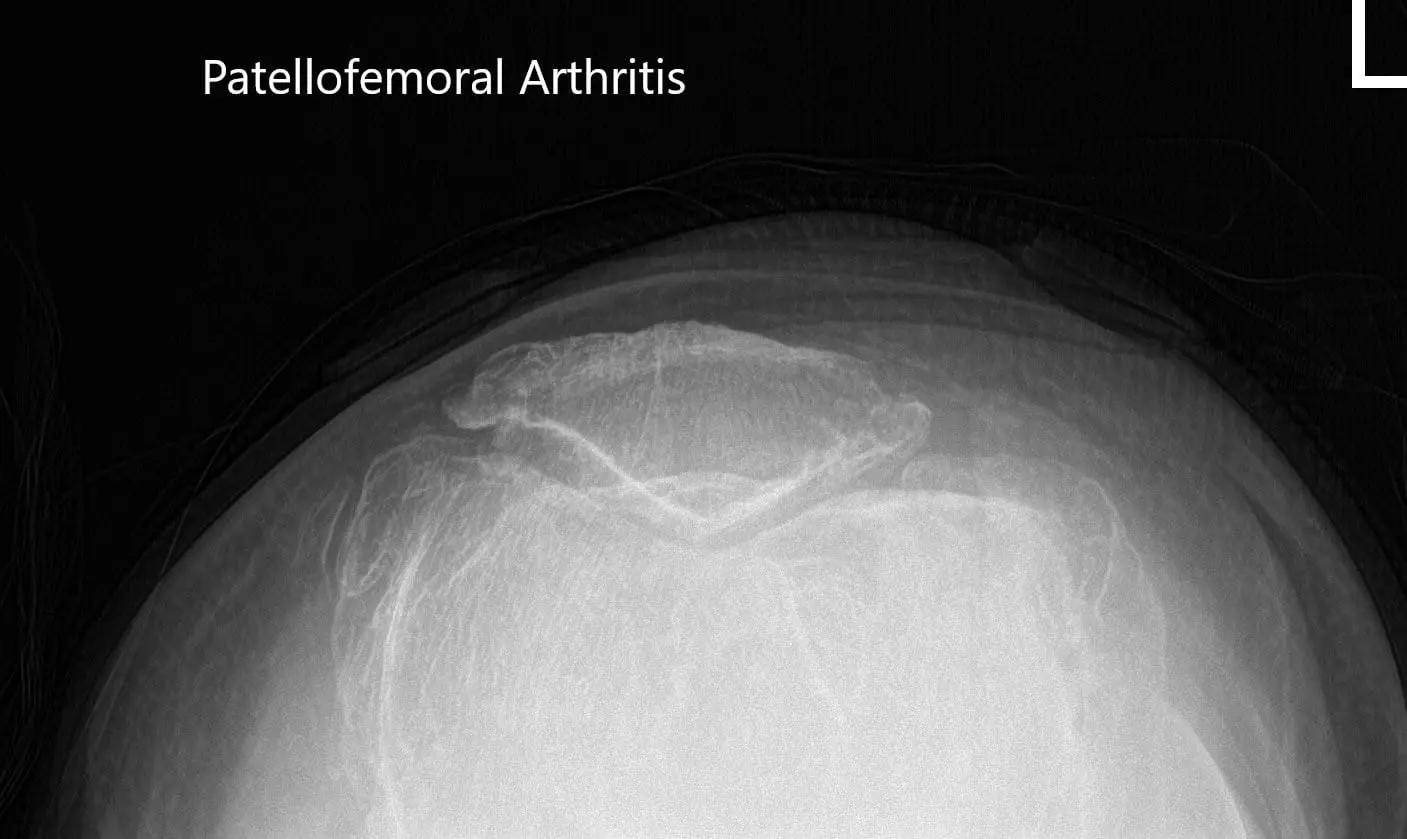

Preoperative merchant views of the bilateral patella showing severe osteoarthritis of the patellofemoral compartment.